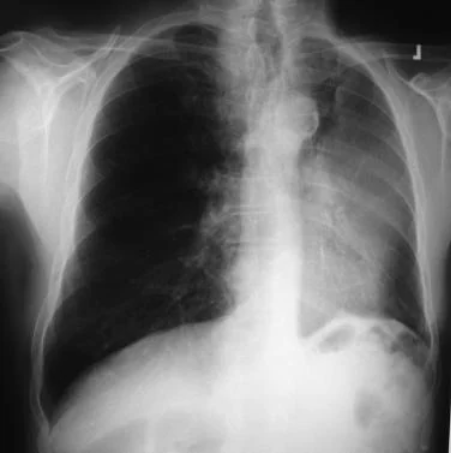

非小细胞肺癌。左下叶非小细胞癌继发的左胸腔积液和容量减少。对胸腔积液取样,发现是恶性的。因此,病变无法手术。